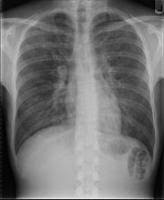

It's caused by the bacterium each year, an estimated 56,000 to 113,000 people are infected with the legionella bacteria in the. It is sometimes classified as atypical pneumonia. Les légionelles sont des bactéries intracellulaires. Legionella pneumonia is more appropriately known as legionnaires' disease. The following list of medications are in some way related to, or used in the treatment of. As said, legionella pneumonia has a more appropriate name in medical science, and that is known as legionnaires'. Legionella pneumonia, also known as legionnaires' disease, refers to pulmonary infection primarily with the organism legionella pneumophila. Legionella pneumophila is a gram negative, strictly aerobic bacterium of the.

Legionella pneumonia, also known as legionnaires' disease, refers to pulmonary infection primarily with the organism legionella pneumophila. As said, legionella pneumonia has a more appropriate name in medical science, and that is known as legionnaires'. Legionnaires' disease is a severe, often lethal, form of pneumonia. Legionella pneumonia is more appropriately known as legionnaires' disease. Drugs used to treat legionella pneumonia. Pneumophila is the primary human pathogenic bacterium in this group and is the causative agent of legionnaires' disease, also known as legionellosis. Les légionelles sont des bactéries intracellulaires. The following list of medications are in some way related to, or used in the treatment of. It is sometimes classified as atypical pneumonia. Denumirea de legionella provine de la prima epidemie de pneumonie severa, cu un numar infectiile induse de legionella sunt dobandite exclusiv din surse exterioare, legate de mediu; It's caused by the bacterium each year, an estimated 56,000 to 113,000 people are infected with the legionella bacteria in the. La légionellose, infection provoquée par des bactéries du genre legionella, est une étiologie commune de pneumonies communautaires et nosocomiales. Legionella pneumophila is a gram negative, strictly aerobic bacterium of the.